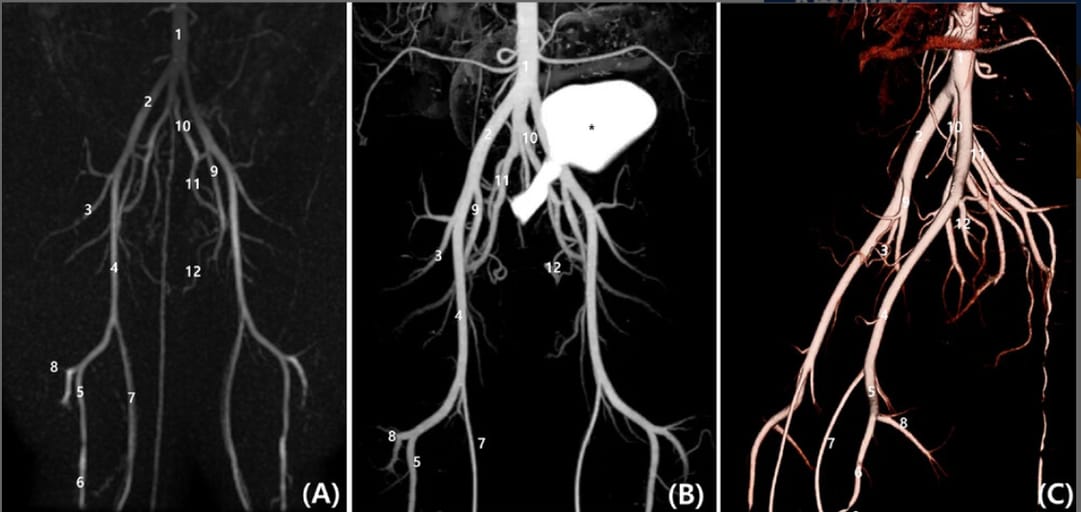

A, Dorsal planes Time-Resolved Imaging of Contrast Kinetics (TRICKS), (B) postprocessed subtraction CT angiography (CTA) maximum intensity projection image, and (C) sagittal plane of three-dimensional reconstructed CTA images (C). The subtraction reconstruction image was generated using a semi-automatic bone-subtraction method in a software program (Xelis, Infinitt). Both TRICKS and CTA demonstrate the following arterial branches: aortic bifurcation (1), external iliac (2), lateral circumflex femoral (3), femoral (4), popliteal (5), cranial tibial (6), saphenous (7), distal caudal femoral (8), deep femoral (9), internal iliac (10), gluteal (11), and internal pudendal arteries (12). The asterisk (*) indicates the urinary bladder with contrast medium.

TRICKS yielded image quality and vascular visualization comparable to CTA, particularly in distinguishing arteries from veins and visualizing smaller vessels. TRICKS significantly outperformed TOF and was superior or equivalent to phase-contrast MRA in most qualitative parameters. CTA had the shortest acquisition time (~20 s), followed by TRICKS (~130–150 s), while TOF was the longest (~670–880 s). TRICKS also allowed dynamic assessment of blood flow phases. Phase-contrast MRA performed well for large vessels but had limited visualization of small branches and vessel continuity. TOF showed the poorest image quality due to flow-related artifacts. Observer agreement across all evaluation categories was excellent (ICC > 0.8).